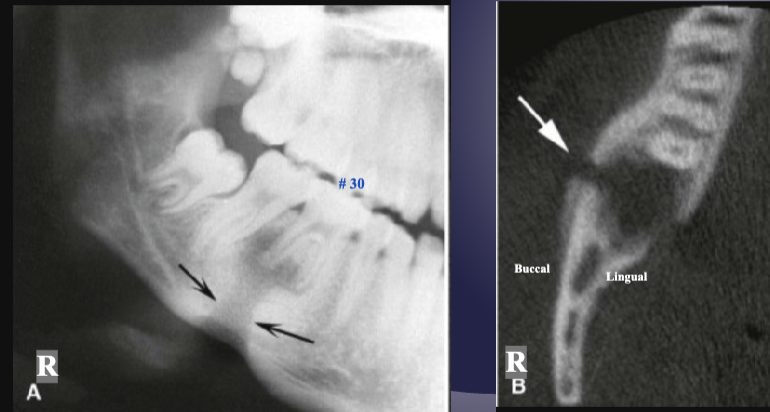

differentiate the pathology for #30 + #31

#30: apical rarefying osteitis

#31: developing tooth w/ open root apex

what’s the arrow pointing to

periosteal new bone formation

what is the black arrow pointing to

large sequestra caused by acute osteomyelitis